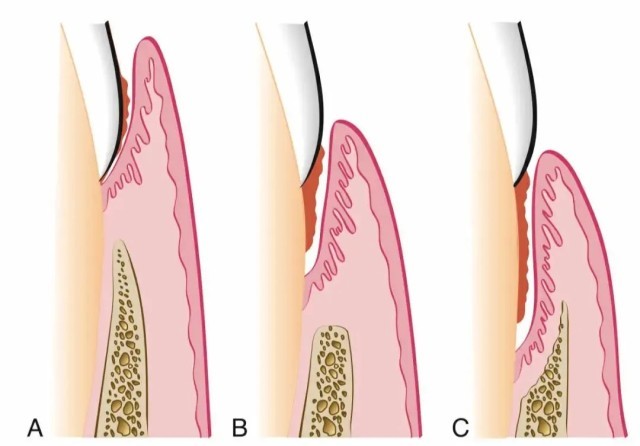

牙周炎一开始出现的症状是:牙龈发红,刷牙时有点出血,啃一口苹果后发现留下一圈血印子。

如果不在意,牙龈开始退缩,牙齿缝显露出来。

之后,牙齿会出现松动,时不时有脓液流出来。

再后来,牙齿和牙齿之间的缝隙越来越大,而之前松动的牙齿开始摇摇晃晃,有的人还会出现牙痛。这时候吃药止痛,已经无济于事。随着牙周炎的进展,病变越来越深入牙龈深处。

△随着牙周炎的进展,病变越来越深入牙龈深处。